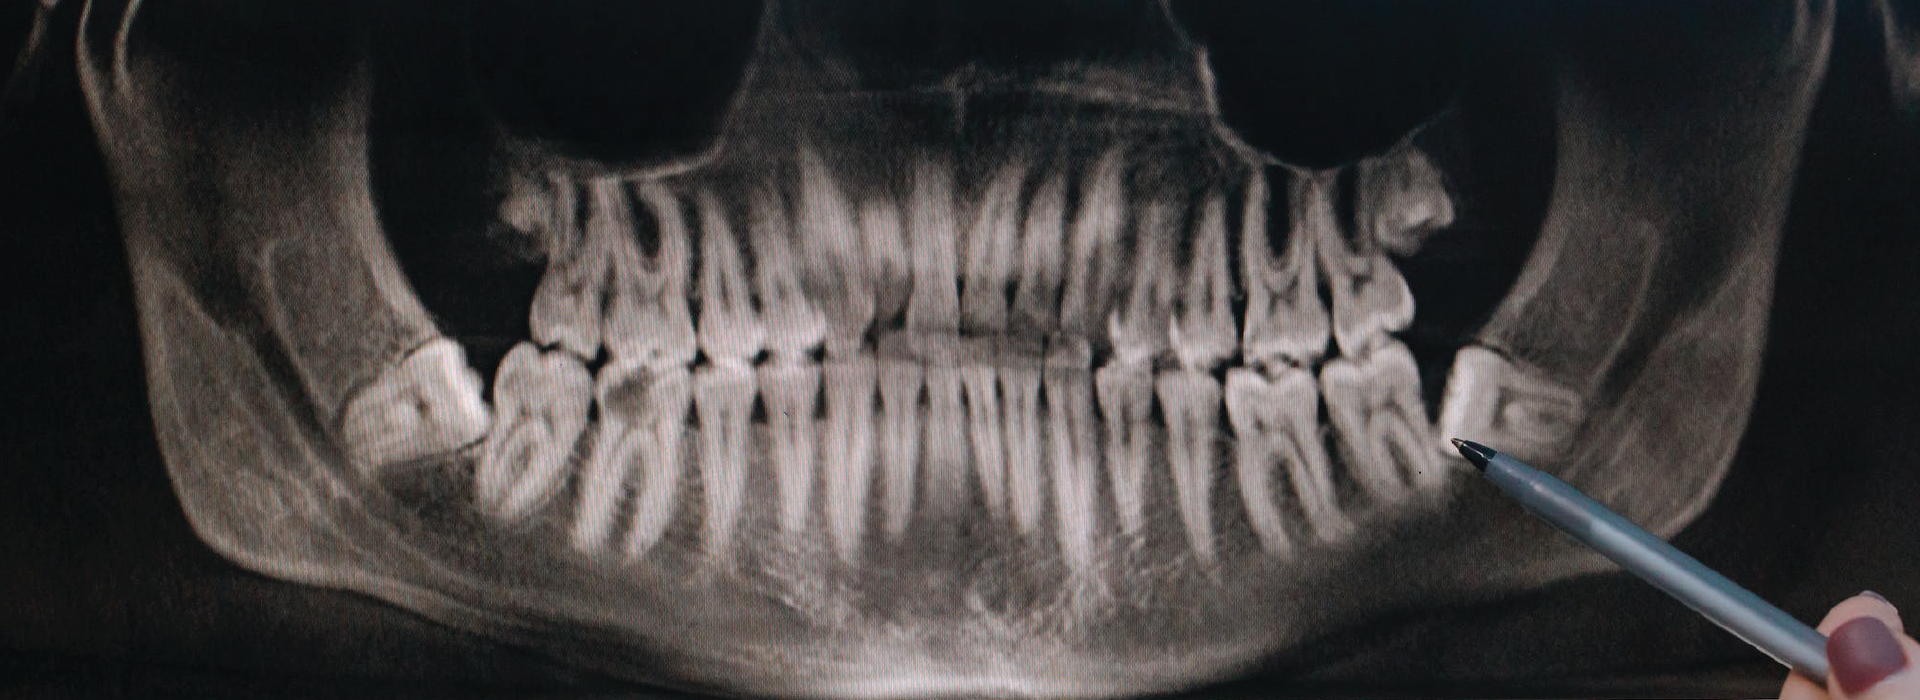

Röntgen ve Görüntüleme

Panoromik Film